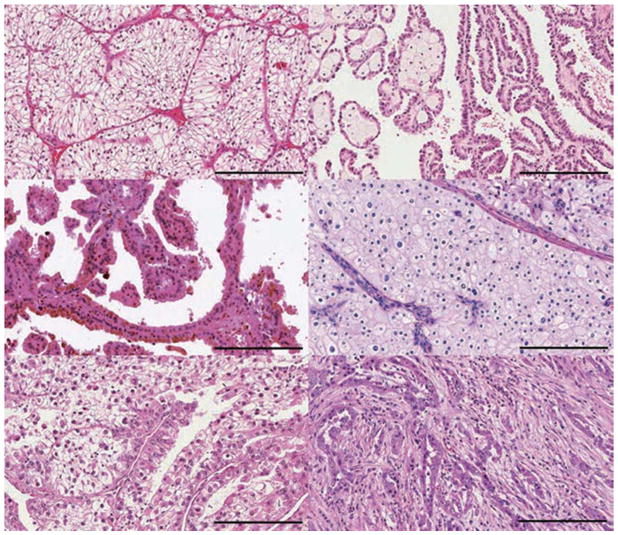

图1:RCC 的不同亚型

大约 75% 的肾细胞癌 (RCC) 是: a、| 透明细胞肾细胞癌(RCC)(ccRCC)。b、 | 乳头状肾细胞癌(RCC)约占所有肾癌的 15%,根据染色特征分为两种类型:b | 1 型(嗜碱性)和 c | 2 型(嗜酸性)。d | 嫌色细胞肾细胞癌(RCC)约占肾肿瘤的 5%。其他次要亚型包括 e | MiT 家族易位肾细胞癌(RCC)和 f | 集合管 RCC。其他次要亚型包括髓质 RCC、透明细胞乳头状 RCC、获得性囊性病变相关 RCC、肾小管囊性 RCC、粘液性管状和纺锤体 RCC、琥珀酸脱氢酶缺陷型 RCC、遗传性平滑肌瘤病、肾细胞癌相关肾细胞癌(RCC)和嗜酸细胞瘤。不属于这些类别的肿瘤被指定为未分类 RCC。比例尺 = 200 微米。